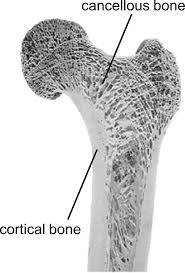

31)define cancellous bone. (કેન્સેલસ બોન ને વ્યાખ્યાયિત કરો).

• આ એક લેટીસ જેવું બોન ( lattice bone ) સ્ટ્રક્ચર છે.